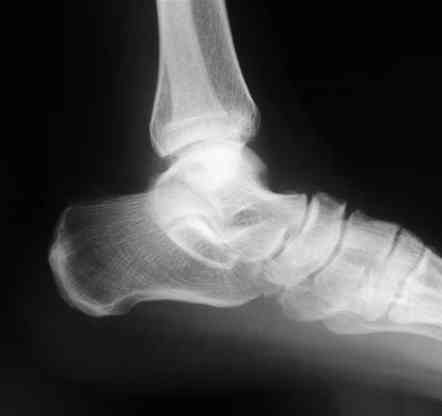

В приложении отправляю послеопер. снимки бедра и лодыжки обсуждаемого вчера больного.

В приложении послеоперационные картинки.